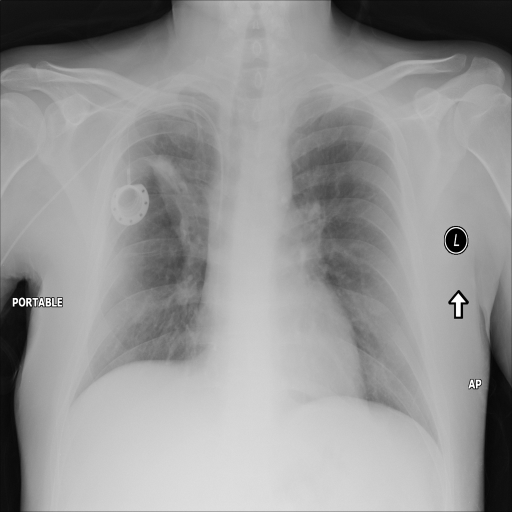

In Fig. 1, we show four ϵitalic-ϵ\epsilon-LDP-processed CXR images of clinical cases obtained with the image domain LDP, which directly imposes the Laplace mechanism on the input image, with different privacy budgets together with the original images. Fig. 2 shows four ϵitalic-ϵ\epsilon-LDP-processed CXR images of clinical cases obtained with DP-GLOW and different privacy budgets together with the original images. In case 1 for DP-GLOW, there is decreased permeability in the bilateral hilar regions. Although this hilar opacity tends to be preserved with a larger privacy budget, the entire image is degraded when the privacy budget becomes 101HWsuperscript101𝐻𝑊10^{1}\cdot H\cdot W. A similar tendency is observed in the images of all the four cases for DP-GLOW; for example, in case 4 with ϵ=101HWitalic-ϵsuperscript101𝐻𝑊\epsilon=10^{1}\cdot H\cdot W, the lung opacity suggesting pneumonia in the right lower lung field is well preserved, while the entire image is degraded.